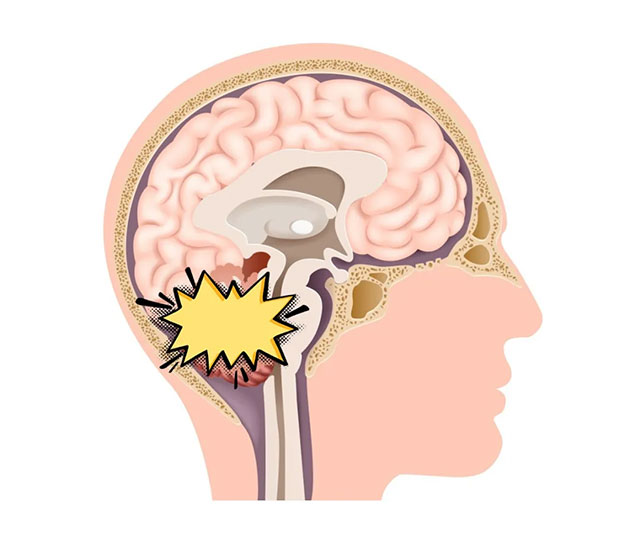

小腦,是運動的重要調(diào)節(jié)中樞,它使人體運動保持協(xié)調(diào)。同時,小腦在維持身體平衡方面也起著重要作用。而一旦小腦周圍腦組織或相關(guān)聯(lián)的神經(jīng),因各種原因(如小腦萎縮、腫瘤等)被破壞或損傷,患者可表現(xiàn)出頭暈、步態(tài)不穩(wěn)、肢體活動不協(xié)調(diào)、言語功能障礙等小腦性共濟失調(diào)癥狀。小腦發(fā)育不良性神經(jīng)節(jié)細胞瘤,就是各類小腦腫瘤中相當(dāng)少見的一種,但其對患者健康的威脅卻不容小覷。

小腦發(fā)育不良性神經(jīng)節(jié)細胞瘤,是一種起源于小腦皮層、緩慢進展為特征的占位性病變。該病相當(dāng)少見,2016年WHO最新分類仍將其歸類于“神經(jīng)元和混合神經(jīng)元—神經(jīng)膠質(zhì)腫瘤”,WHO分級為I級,即為良性腫瘤。

上海藍十字腦科醫(yī)院神經(jīng)外科主任沈建康教授表示,小腦發(fā)育不良性神經(jīng)節(jié)細胞瘤具有發(fā)育畸形和良性腫瘤的一些特點,如進展緩慢、早期多無癥狀等,因而起病初期不易被患者覺察。隨著腫瘤生長,可出現(xiàn)小腦病變癥狀,如頭暈頭痛、嘔吐、記憶力下降、小便急迫等。約40%的患者會出現(xiàn)小腦受壓體征,如步態(tài)不穩(wěn)、行走困難等共濟失調(diào)癥狀,與小腦萎縮患者的一些臨床表現(xiàn)相類似。